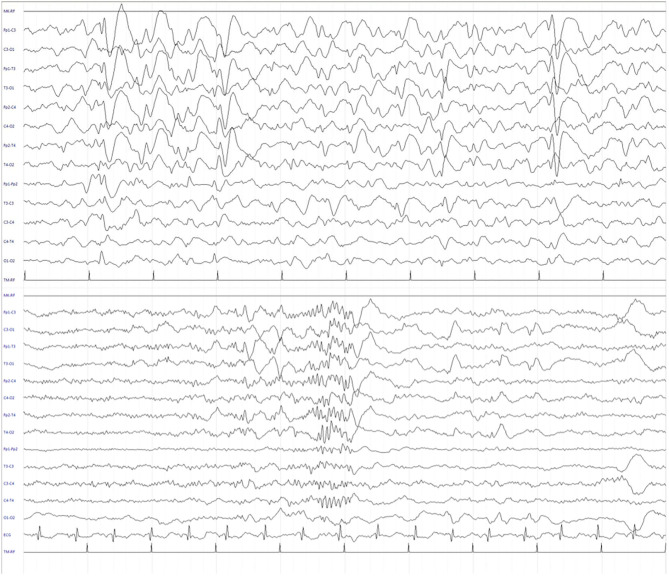

We report the case of a 13-year-old girl born from not consanguineous parents. She was born preterm (32 weeks of gestational age) after a pregnancy complicated by threatened miscarriage. The patient showed microcephaly, facial dysmorphisms (depressed nasal bridge, broad nose, wide and prominent open mouth, puffiness around eyes and lips, and full cheeks), failure to thrive, recurrent kidney stones, and scoliosis. A severe developmental delay became evident since birth. Neurologically, she reported flaccid tetraparesis without achievement of deambulation. Language skills were merely characterized by vocalizations. An echocardiogram revealed peripheral pulmonary artery stenosis. She was hospitalized for severe respiratory distress and neonatal seizures at birth time, requiring treatment with phenobarbital. At 10 months of age, she showed infantile spasms and, subsequently, the seizures presented high variability in intensity and semeiology, suggesting a diagnosis of drug-resistant epileptic encephalopathy. Multiple-label and off-label antiepileptic drugs (AEDs) were prescribed without clinical effects (Figure 1). At 2 years of age, a normal female karyotype was confirmed by proper testing, while fluorescent in situ hybridization (FISH) revealed typical WBS deletion del (ref. 7) (q21q21), confirming WBS diagnosis. A first brain magnetic resonance imaging (MRI) was obtained on the first day of life, but it was not informative. A new MRI was performed at the age of 11 years and revealed a thinning of the corpus callosum, reduced brainstem size, thinning of periventricular white matter, and bilateral optic nerve hypoplasia. At the age of 12 years, Agilent Human Genome CGH Microarray Kit 4 × 180K (with an overall median probe space of 13 kb) revealed a de novo very large deletion [del 7q11.21q21.11 (66849415_86269865) × 1 of 19.4 Mb]. Subsequently, we performed whole-exome sequencing (WES). The patient and her parents DNA were analyzed by OneSeq protocol, via Illumina HiSeq 2500, but any mutation in known genes associated with epileptic encephalopathy was reported. At the age of 13 years, the patient was readmitted to our Child Neurology Unit at A.O.U. “G. Martino” Hospital, Messina, because of a marked increase in frequency and severity of seizures (four to five seizures/day), with variable semiology (focal seizures or flexion–extension spasms mostly associated with cyanosis, bradycardia, and desaturation) and duration (from few seconds up to 20 min), often requiring treatment with endorectal diazepam and/or hydrocortisone. She was treated with primidone, carbamazepine, diazepam, and levetiracetam (LEV). Interictal electroencephalogram (EEG) showed quasi-continuous spike-and-wave complex in the frontocentral region (Figure 2). Primidone, diazepam, and carbamazepine were progressively reduced and discontinued. LEV was titrated up to 1,200 mg/day (63 mg/kg), pregabalin up to 50 mg/die (2.6 mg/kg); clobazam 20 mg/die (1 mg/kg) was added but without clinical benefit. On the 20th day of admission, the patient was started on Epidiolex—a new, 99% pure, oral CBD extract (Epidiolex, GW Pharmaceuticals, London, UK) −50 mg twice daily, then titrated up to 200 mg twice daily (20 mg/kg). After 3 months of CBD treatment, seizure frequency was reduced up to one to three attacks/week and characterized by sporadic and brief clusters of flexor-extensor spasms. No episode of cyanosis, bradycardia, and desaturation was reported. The patient did not need acute diazepam or hydrocortisone treatment. Moreover, an evident improvement of patient awareness and social interaction were noticed. An enriched vocalization and a gain of better postural and gross motor skills (reaching of sitting or crawling postures) were also noted. A new EEG was performed revealing an improvement in cerebral activity and a mild reduction of EEG abnormalities in comparison with her previous EEG (Figure 3). Specifically, the following findings were recorded: (i) theta-alpha activity was more frequently detected in awake; (ii) sleep spindles and K-waves were mainly noted in sleep compared to the previous registration; and (iii) the frequency of EEG abnormalities was reduced by 50 and 20% during sleep and awake, respectively. We scheduled a successive control visit after a 6-month CBD treatment; however, unexpectedly, she died at the end of June in another hospital due to complicated pneumonia. The patient’s parents did not refer changes in her neurological clinical picture compared to the last valuation.